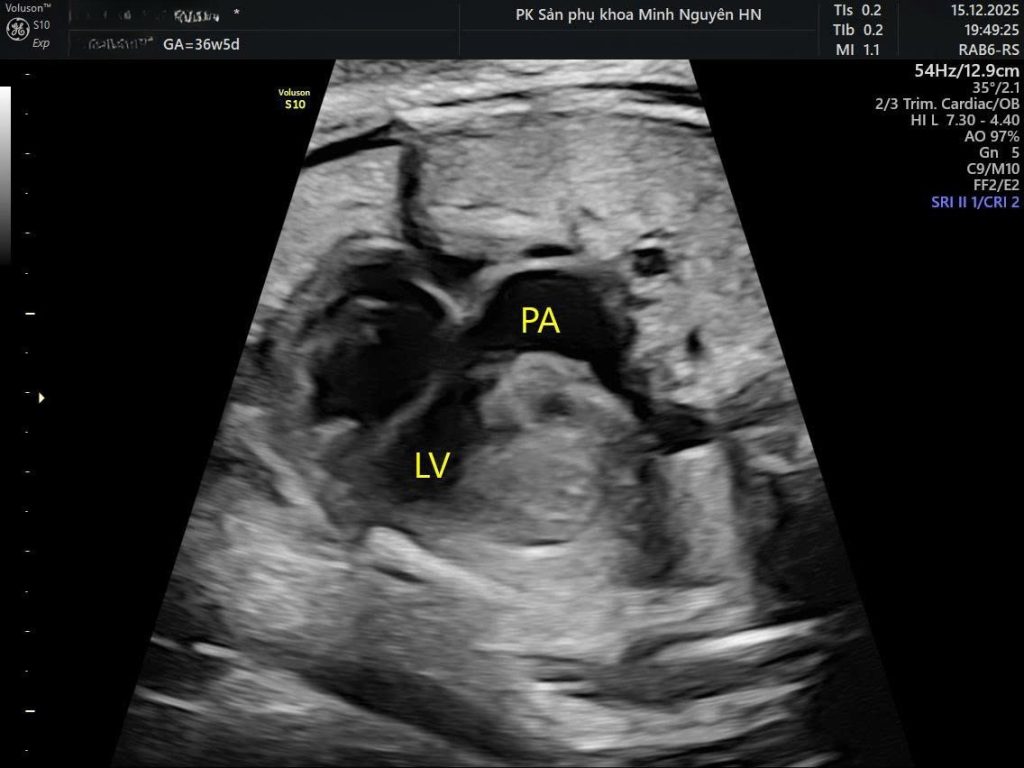

Đảo gốc động mạch là tên gọi khác của chuyển vị đại động mạch hoàn toàn, thường gặp nhất là thể d-TGA.

Trong dị tật này:

- Động mạch chủ xuất phát từ thất phải

- Động mạch phổi xuất phát từ thất trái

Hai đại động mạch không còn bắt chéo nhau như tim bình thường mà chạy song song.

- Mặt cắt đường ra hai thất

- Mặt cắt ba mạch máu và khí quản

Bình thường hai đại động mạch bắt chéo nhau tạo hình chữ X.

Trong đảo gốc động mạch, hai mạch chạy song song tạo hình chữ I.